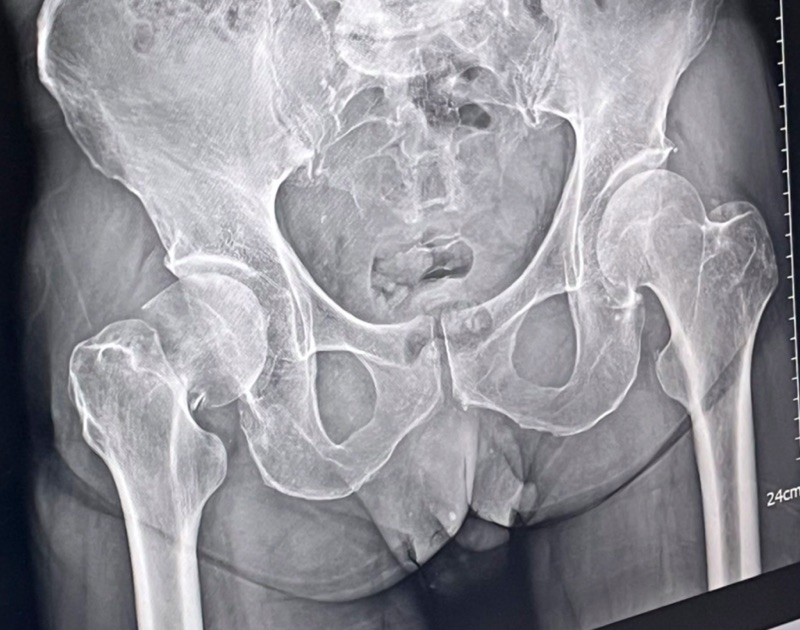

กระดูกสะโพกหัก (Hip Fracture) เป็นภาวะที่พบได้บ่อยในผู้สูงอายุ โดยเฉพาะในผู้ที่มีภาวะกระดูกพรุน (Osteoporosis) ซึ่งทำให้กระดูกเปราะบางและหักได้ง่าย แม้จากการหกล้มเพียงเล็กน้อย อาการของภาวะนี้มักรุนแรง ผู้ป่วยไม่สามารถเดินได้ มีอาการปวดมาก และหากไม่ได้รับการรักษาอย่างเหมาะสม อาจเกิดภาวะแทรกซ้อนที่เป็นอันตรายถึงชีวิต

ขึ้นอยู่กับตำแหน่งและลักษณะของกระดูกที่หัก แพทย์อาจเลือกใช้การผ่าตัดวิธีต่างๆ เช่น

1. การยึดกระดูกด้วยโลหะ (Internal Fixation) – ใช้แผ่นโลหะและสกรูช่วยยึดกระดูกให้ติดกัน เหมาะกับผู้ป่วยที่กระดูกยังคงแข็งแรงพอสมควร

2. การเปลี่ยนข้อสะโพกบางส่วน (Hemiarthroplasty) – เปลี่ยนเฉพาะหัวกระดูกต้นขาที่หัก เหมาะกับผู้ป่วยสูงอายุที่มีกระดูกพรุน

3. การเปลี่ยนข้อสะโพกทั้งข้อ (Total Hip Replacement) – เปลี่ยนทั้งข้อสะโพก เหมาะกับผู้ป่วยที่มีข้อสะโพกเสื่อมร่วมด้วย

กระดูกสะโพกหักในผู้สูงอายุเป็นภาวะที่ต้องได้รับการรักษาอย่างเร่งด่วน และการผ่าตัดเป็นทางเลือกที่ดีที่สุด เพราะช่วยลดภาวะแทรกซ้อน ฟื้นตัวเร็ว และช่วยให้ผู้ป่วยกลับมาเดินได้อย่างปลอดภัย การเลือกวิธีผ่าตัดที่เหมาะสมขึ้นอยู่กับอายุ สุขภาพโดยรวม และลักษณะของกระดูกที่หัก ดังนั้น หากเกิดภาวะนี้ขึ้น ควรรีบพบแพทย์เพื่อรับคำแนะนำและการรักษาที่เหมาะสมที่สุด